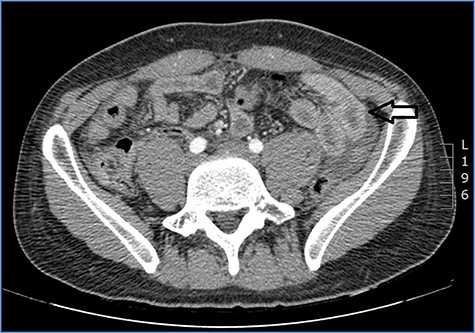

Abdominal CT scan showing distention, bundling and thickening of some small bowel loops in the left quadrant (arrow).

fluid collection in the peritoneal cavity. Subsequent CT confirmed the presence of diffuse fluid collection in the peritoneal cavity (Fig. 1) but no free air, with distention, bundling and thickening of some small bowel in the left quadrant (Fig. 2). The patient was therefore admitted for supporting therapy (intravenous fluids and antibiotics) with the suspicion of cocaine-induced small bowel ischemia. Twelve hours later, signs and symptoms of diffuse peritonitis developed: worsening diffuse abdominal pain with rebound guarding at examination, a significant increase in WBCs count (16.15 × 103/μl) and neutrophilia (88%), lengthening of coagulation times (INR: 1.68; aPTT: 33.0 s) and increase in fibrinogen (430 mg/dl) and D-Dimer (2275 ng/ml). Therefore, urgent surgical exploration of the abdomen through a three-port open laparoscopic approach was performed, confirming the presence of 1200 ml of exudative fluid and fibrin clots (Fig. 3). Several adhesions between greater omentum, abdominal wall and small bowel underwent blunt dissection. Thorough exploration of the small bowel revealed two ischemic segments located at about 50 and 100 cm from the Treitz ligament (Fig. 4). The large bowel appeared normal. The existence of non-visible gastro-duodenal perforations was ruled out with the administration of 500 ml of saline with 20 ml of methylene blue through the nasogastric tube. An iv bolus of sodium heparin, 10 000 IU, was then administered, performing a 30-min peritoneal lavage with 5 l of saline solution at 37°C. After reaspiration of peritoneal lavage, a new complete exploration of the small bowel was performed, showing complete revascularization of the two ischemic small bowel segments (Fig. 5). Two tubular drainage tubes were placed in the left and right colic gutters. Culture examination of peritoneal exudate was positive for multi-sensitive Escherichia coli and Enterococcus, thus confirming bacterial translocation peritonitis. Postoperative therapy included the administration of iv piperacillin–tazobactam and subcutaneous low molecular weight heparin. Postoperative recovery was smooth, with oral feeding on the second postoperative day (POD), drainage removal on POD 3, complete bowel function restored on POD 4 and home discharge on POD 5. At 15- and 30-day-follow-up, the patient showed full recovery, being now followed by a specialized support structure for his drug abuse.